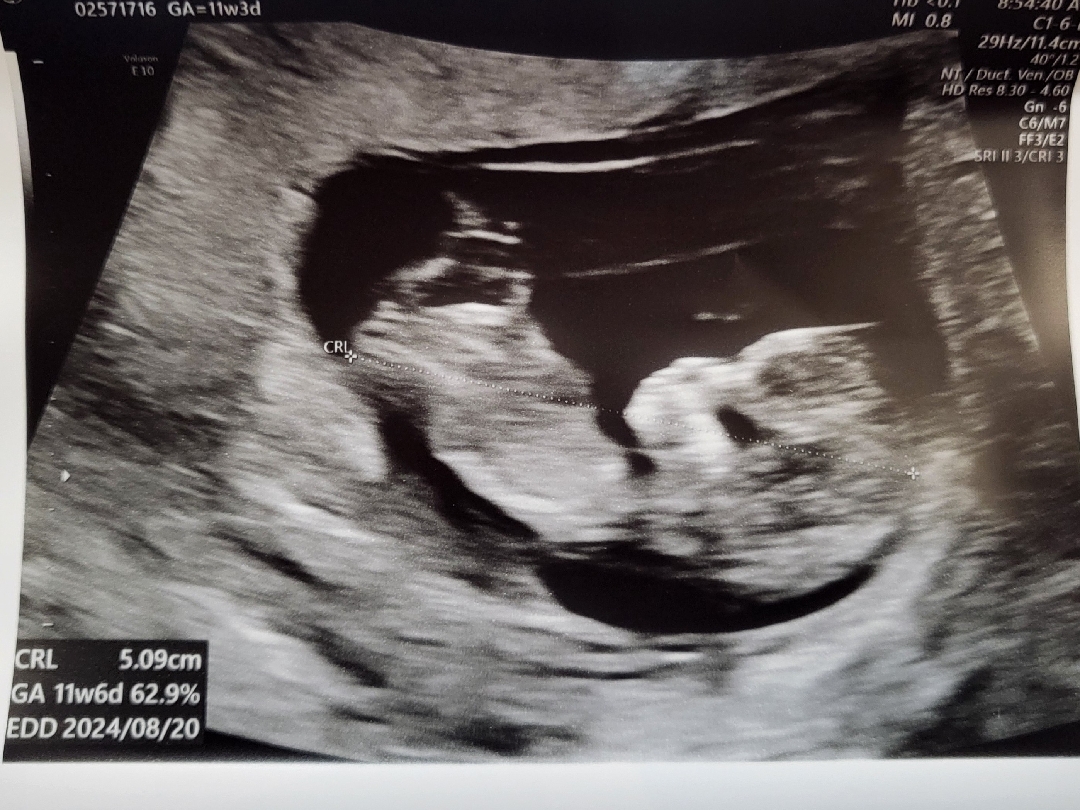

각도법 좀 봐주세여 ㅠㅠㅎ

담당 선생님께서 성별은 32주에 알려주신다구..^^; ㅠㅠ 혹시 성별이 보이실까여

갠적으론 딸에 한표요!